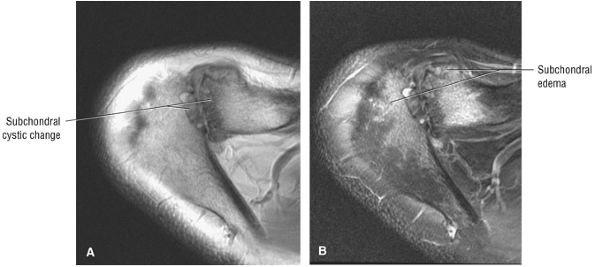

-

Acromial thickness is important in planning subacromial decompression procedures.

The AC joint may hypertrophy, but it is not responsible for true impingement.